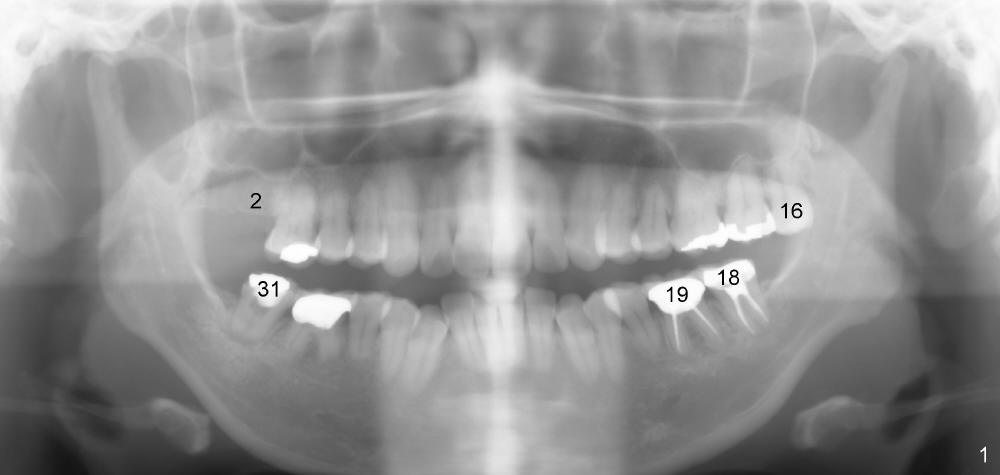

A 43-year-old lady develops tinnitus recently. Her primary care physician suspects that it is related to root canal therapy for the teeth #18 and 19 (Fig.1). Several more treatment is needed: extraction of #16 (Fig.1), RCT of #31 (Fig.1,3) and implant for #2 (Fig.1,2). Sinus lift and probably bone expansion may be required for #2 implant placement. Does usage of osteotomes worsen tinnitus, similar to occasional occurrence of vertigo after bone expansion?